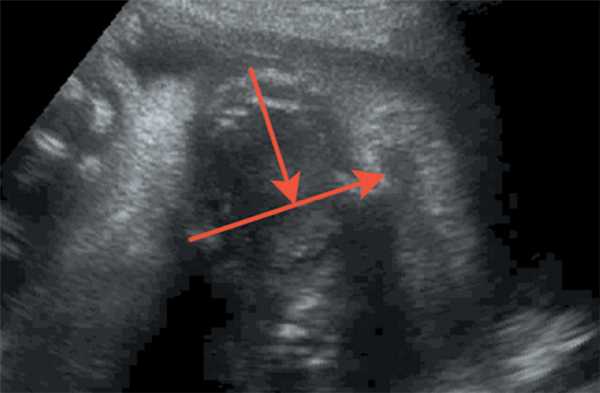

Измерение соотношения ширины нижней челюсти и ширины верхней челюсти производилось в осевом положении на уровне альвеолярного отростка 10 мм кзади от передней костной границы (рис. 5, 6). Среднее значение этого коэффициента равно 1,02 ± 0,12 (SD), следовательно, коэффициент меньше 0,78.

Рис. 5. Длина нижней челюсти / Fig. 5. Length of the lower jaw